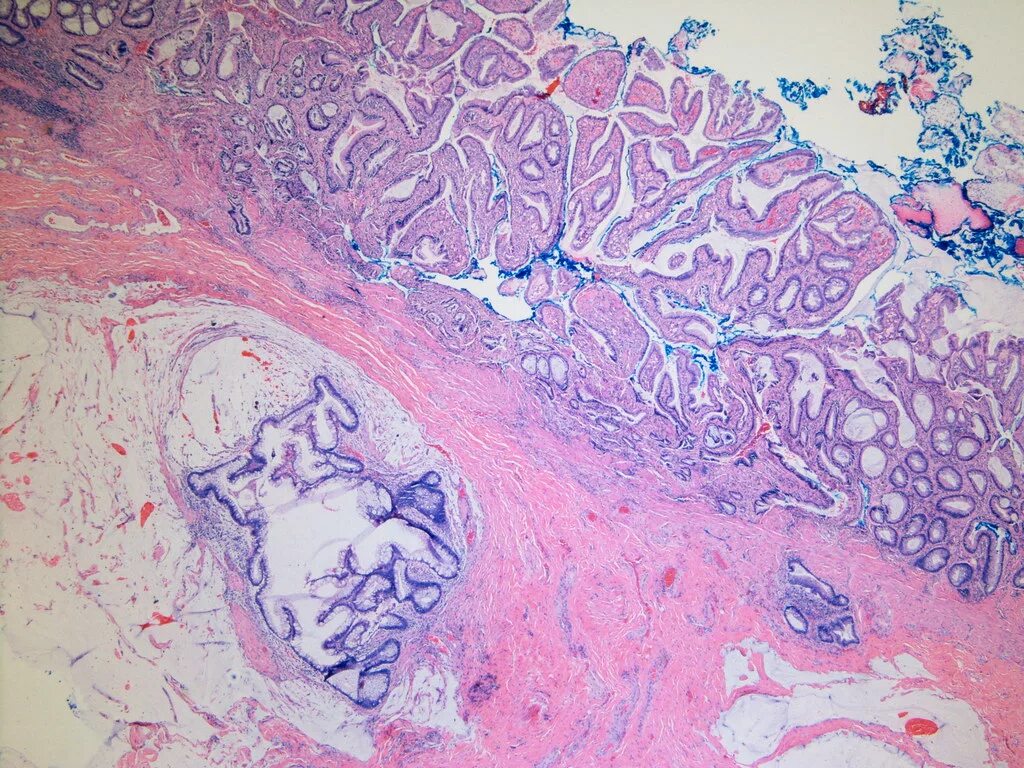

Язва гистология